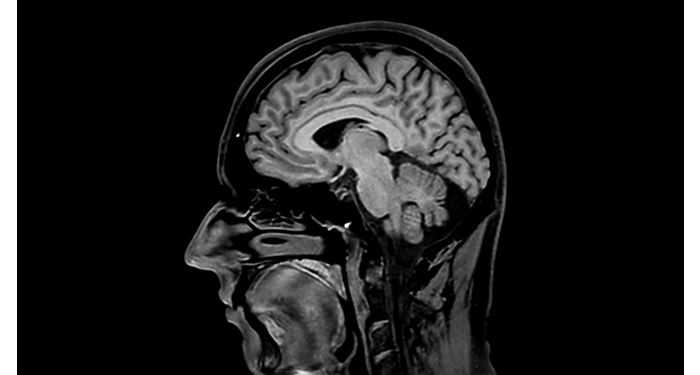

Protocolos cerebrales de UVM actualizados con los últimos métodos

UVM aprecia los últimos métodos neurológicos de resonancia magnética para el diagnóstico y el flujo de trabajo.